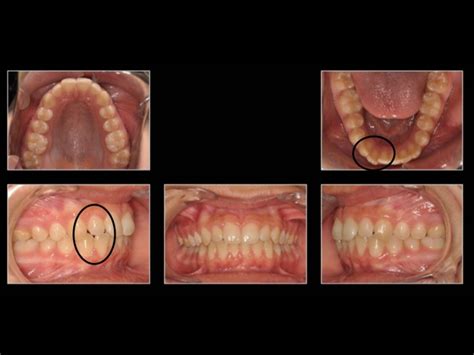

Solo Tengo Un Diente Torcido, Solo tengo UN DIENTE TORCIDO: ¿necesito usar BRACKETS ¿Y si es diente de leche | #Shorts, 1.37 MB, 01:00, 10,128, Dentalk!, 2021-12-09T22:00:10.000000Z, 3, Dientes torcidos.¿Soluciones? - Clínica Birbe, birbe.org, 1200 x 800, jpeg, WebLos dientes torcidos son un problema común en la población, sobre todo si hablamos de los niños: todos los padres suelen estar muy preocupados por el hecho. WebTras someterte a un tratamiento de ortodoncia, tus dientes ya no estarán apiñados o torcidos. Podrás mejorar la higiene de tus dientes, prevenir problemas., 20, solo-tengo-un-diente-torcido, Novedades y Muebles WebLos dientes torcidos son un problema común en la población, sobre todo si hablamos de los niños: todos los padres suelen estar muy preocupados por el hecho. WebTras someterte a un tratamiento de ortodoncia, tus dientes ya no estarán apiñados o torcidos. Podrás mejorar la higiene de tus dientes, prevenir problemas.

WebEn primer lugar, comprobemos que no hay ningún problema físico que cause ese diente torcido. Un diente torcido puede ser el resultado de un traumatismo. WebOrtodoncia para un solo diente. Hola, a mi me pasaba lo mismo que a ti, tb tengo un diente lateral bastante torcido y al reir se ve mucho. Después de mucho dar.

WebA partir de los 5 o 6 años se empiezan a caer los dientes de leche y ves que los nuevos dientes no salen donde estaban los anteriores. Ahora, salen mal colocados,. Web¿Es posible usar ortodoncia en los dientes de leche? ¿Es necesario usarla si solo tengo un diente torcido? ¿Me pueden colocar brackets si me acaban de extrae... Web1.5K views, 12 likes, 2 loves, 0 comments, 0 shares, Facebook Watch Videos from Clínica Dental Pardiñas: ¿Es posible usar ortodoncia en los dientes de leche? ¿Es necesario. WebOtras causas para la aparición de los dientes torcidos pueden ser los traumatismos o golpes en la boca en la época de la niñez y otros malos hábitos como chuparse el dedo cuando. WebSi solo existe un ligero apiñamiento con unos pocos meses de tratamiento será suficiente. Si es necesario hacer extracciones o hay dientes incluidos, puede durar más de dos. WebHola, tengo toda la boca y dientes en excelente estado nunca tube problemas, solo que al cepillarme los dientes me sangra la encia, pero tengo un diente. WebSi crees que el diente está lo suficientemente flojo para salir sin causar dolor, entonces utiliza un pedazo de gasa esterilizada para agarrar el diente y girarlo. X Fuente confiable. WebLos dientes torcidos pueden causar problemas en el estado de salud de los niños. Más del 50 por ciento de los niños presentan problemas de maloclusión o.

WebSi crees que el diente está lo suficientemente flojo para salir sin causar dolor, entonces utiliza un pedazo de gasa esterilizada para agarrar el diente y girarlo. X Fuente confiable. WebLos dientes torcidos pueden causar problemas en el estado de salud de los niños. Más del 50 por ciento de los niños presentan problemas de maloclusión o. WebRealizar una ortodoncia para corregir un solo diente puede ser algo que nos tengamos que pensar y mucho, a nadie le gusta tener que hacerse nada en la boca debido a que no es.